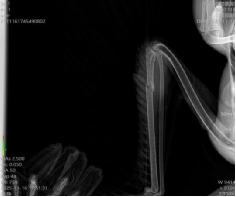

16日,越西县林业和草原局艾永斌一行将黑颈鹤送到西昌学院攀西动物医院,郝桂英快速组织严光文教授、黄增文博士、常卫华、赵影、李昊、李欣虹等专家对黑颈鹤进行诊疗处置,经DR检查、临床检查等内容,确诊黑颈鹤左侧尺骨骨折,左侧腕关节擦伤。

初步救治后的黑颈鹤